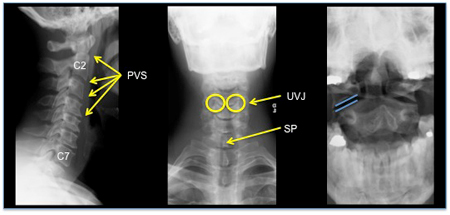

may show cervical spine vertebral misalignment, fracture, and pre-vertebral soft-tissue swelling

may show cervical disc herniation, anterior or posterior ligament disruption, cord compression, spinal canal compromise, and intramedullary T1- and/or T2-weighted hyperintensity and/or hypointensity